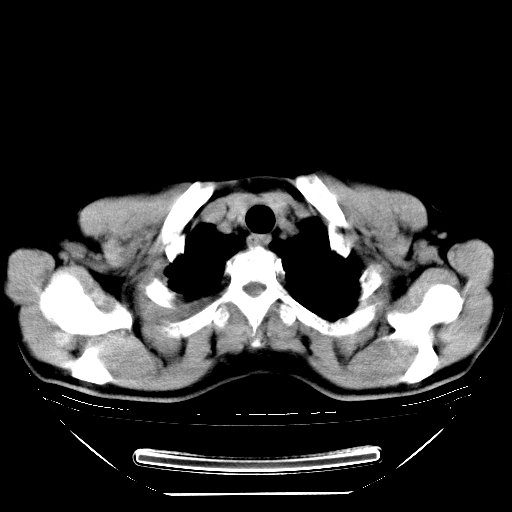

标题: CT21642:男,56岁,咳嗽、咳痰、右侧胸痛一周。 [打印本页]

男,56岁,咳嗽、咳痰、右侧胸痛一周,无发热。

纵膈窗关键层面不全。考虑右上肺继发性tb可能性大。建议查血沉、ppd,痰菌培养。

1)考虑右肺上叶继发性肺结核。2)两肺近胸膜下多发性肺大泡。

补传图像:纵隔窗已补传完。